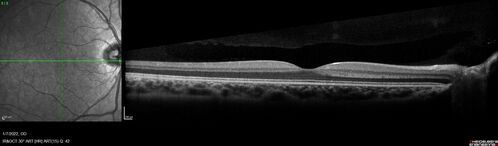

Combined hamartoma of the retina and retinal pigment epithelium

8 year old boy failed vision screening at school. VA 20/20 OD, 20/40 OS

Combined hamartoma of the retina and the retinal pigment epithelium